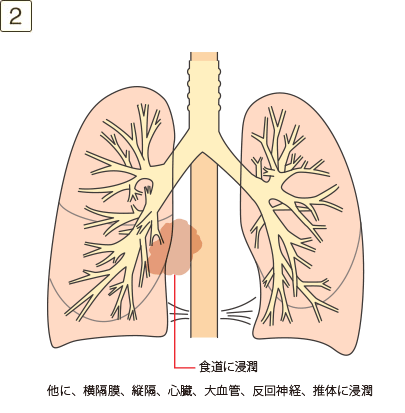

充実成分径>5cmでかつ≦7cm、または充実成分径≦5cmでも以下のいずれかであるもの・壁側胸膜、胸壁(superior sulcus tumor を含む)、横隔神経、心膜のいずれかに直接浸潤・同一葉内の不連続な副腫瘍結節

充実成分径>7cm、または大きさを問わず横隔膜、縦隔、心臓、大血管、気管、反回神経、食道、椎体、気管分岐部への浸潤、あるいは同側の異なった肺葉内の副腫瘍結節